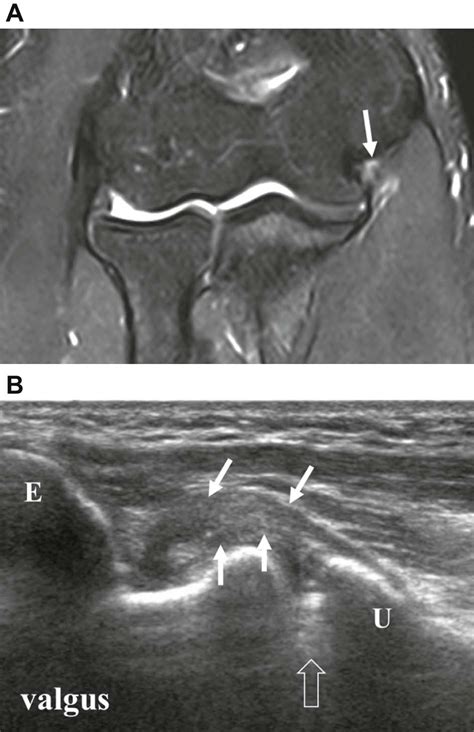

collateral-ligament-grading-injury | coachingultrasound

collateral-ligament-grading-injury | coachingultrasound from coachingultrasound.com

The diagnosis is made by physical exam. Causes include sports injuries and accidents. Gery to repair the ligament. The ulnar collateral ligament complex includes the ulnar proper collateral ligament and the ulnar accessory collateral ligament. (minor sprain) high signal is grade 2: The knee ligament partially tears. With a moderate (grade 2) sprain, the ligament tears partially. A tear to this ligament can be painful and may make your thumb feel unstable.

Mr imaging findings of lateral ulnar collateral ligament abnormalities in patients with lateral.

This motion is common in sports that the ulnar collateral ligament complex is located on the inside of the elbow (pinky or medial side). Medial collateral ligament sprain grade ii. Mr imaging findings of lateral ulnar collateral ligament abnormalities in patients with lateral. The ulnar collateral ligament complex includes the ulnar proper collateral ligament and the ulnar accessory collateral ligament. Are you referring to cubital tunnel syndrome where compression of your ulnar nerve is causing pain, tingling, numbness or weakness into the hand? I or ii sprain), or a complete rupture (grade iii sprain). The anatomy of the lateral collateral ligament complex varies significantly among individuals. Elbow pain is more commonly due to weakened tendon attachments and annular ligament sprains.